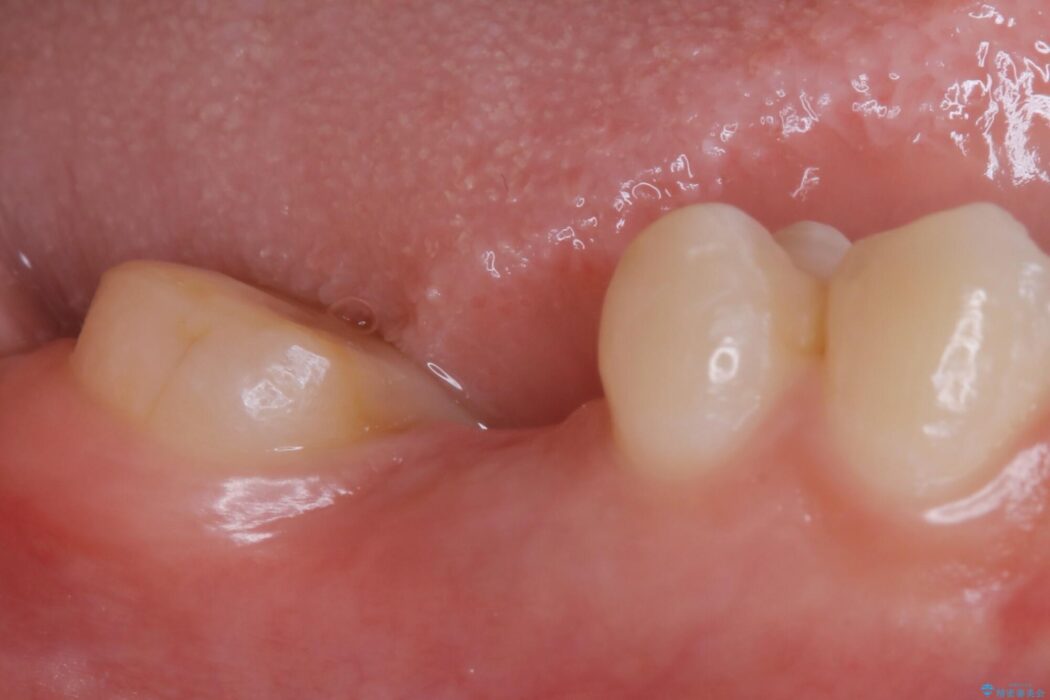

診査した結果、欠損した状態で長期間放置していたことが原因で最高峰の奥歯が欠けた部分に向かって傾斜してしまっていました。

歯が欠損した部分を長期間放置してしまうと、欠損部分に食べ物が入り込んだり、隣り合う歯が倒れこんでしまったり、噛み合うはずの歯が伸びてしまうなどの問題が発生することがあります。